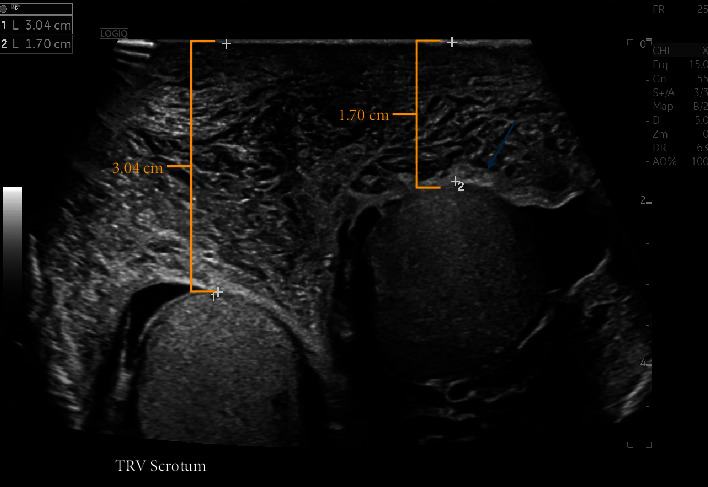

Acquired angioedema with low C1-inhibitor (AAE-C1-INH) is a rare disorder characterized by an acquired deficiency in the C1 esterase inhibitor (C1-INH). This case report describes a 79-year-old patient presenting to the emergency department for painless swelling of his scrotum, penile shaft, and left lower and upper extremities with lab values consistent with acquired angioedema without identifiable lymphoreticular or rheumatic disorder on history, exam, or total body PET scan. Proper diagnosis of AAE-C1-INH is essential to prevent life-threatening airway compromise, ensure proper therapy, and exclude lymphoreticular disorders as the etiology of AAE-C1-INH.